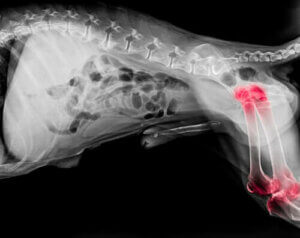

Leddgikt hos hunder

Eksperter mener at omtrent én av fem hunder lider av leddgikt. Selv om denne leddtilstanden kan dukke opp i alle aldre, er den mer vanlig hos eldre hunder. Stort sett er leddgikt en degenerativ sykdom som forårsaker betennelse i både albue- og skulderledd.

Noen vanlige symptomer på leddgikt inkluderer:

- Vanskeligheter med å sette seg eller reise seg

- Stive lemmer

- Tegn på smerte når berørte områder berøres (piping, knurring osv.)

- Motvilje til å gå opp trapper eller takle andre hindringer